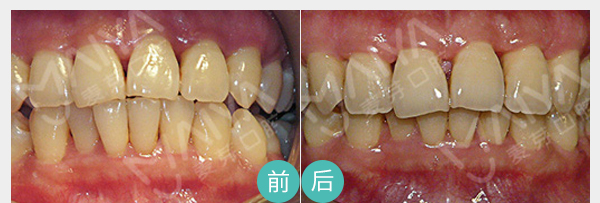

麦芽辩证施治,解决牙齿敏感

• 麦芽脱敏治疗

• 麦芽龈下刮治

• 麦芽显微根管治疗

用探针在牙面上可找到过敏点,除针对病因进行治疗外,局部可用氟化钠药物、氨硝酸银等脱敏药物进行涂擦脱敏治疗。

适应症:轻微牙体敏感

麦芽龈下刮治术是用比较精细的龈下刮治器刮除位于牙周袋内根面上的牙石和菌斑,舒适无痛微创愈合快、深度去除牙龈层牙垢

适应症:牙龈萎缩、牙周炎症 导致的牙体敏感

通过机械和化学方法去除根管内的大部分感染物,并通过充填根管、封闭冠部,防止发生根尖周病变或促进已经发生的根尖周病变的愈合。

适应症:牙髓炎、深度龋齿等